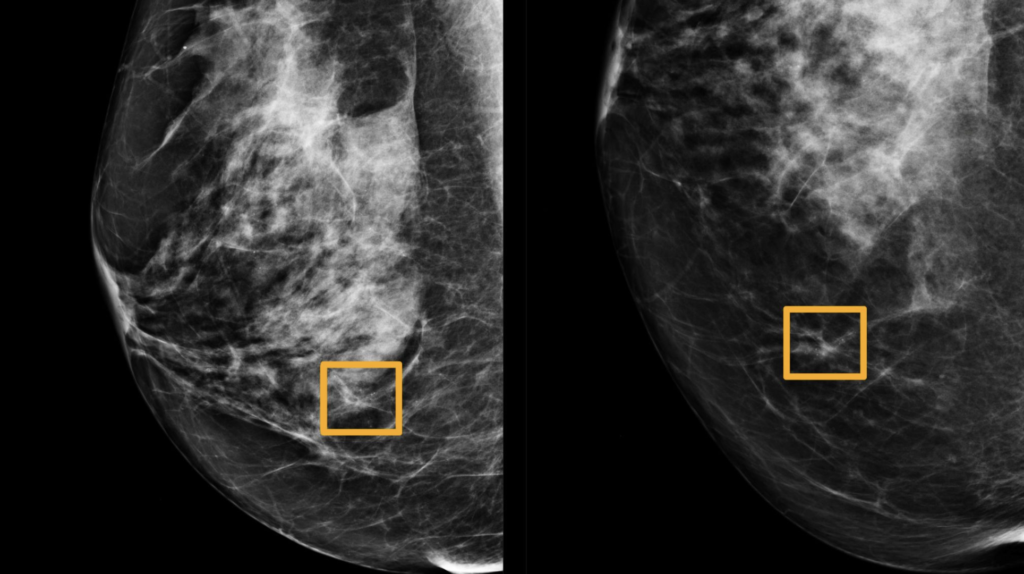

An artificial intelligence program was developed by Google that outperforms clinical specialists in detecting breast cancer in mammograms, according to researchers.

The research demonstrated the AI may identify cancers using a similar amount of precision to radiologists while decreasing the amount of false-positive outcomes by 1.2 percent in the UK-based group and 5.7 percent at the US-based group.

Additionally, it cut the number of false negatives, in which evaluations are classified as ordinary, by 2.7 percent in the united kingdom group and 9.4 percent in America group. These gaps reflect the ways that mammograms are read.